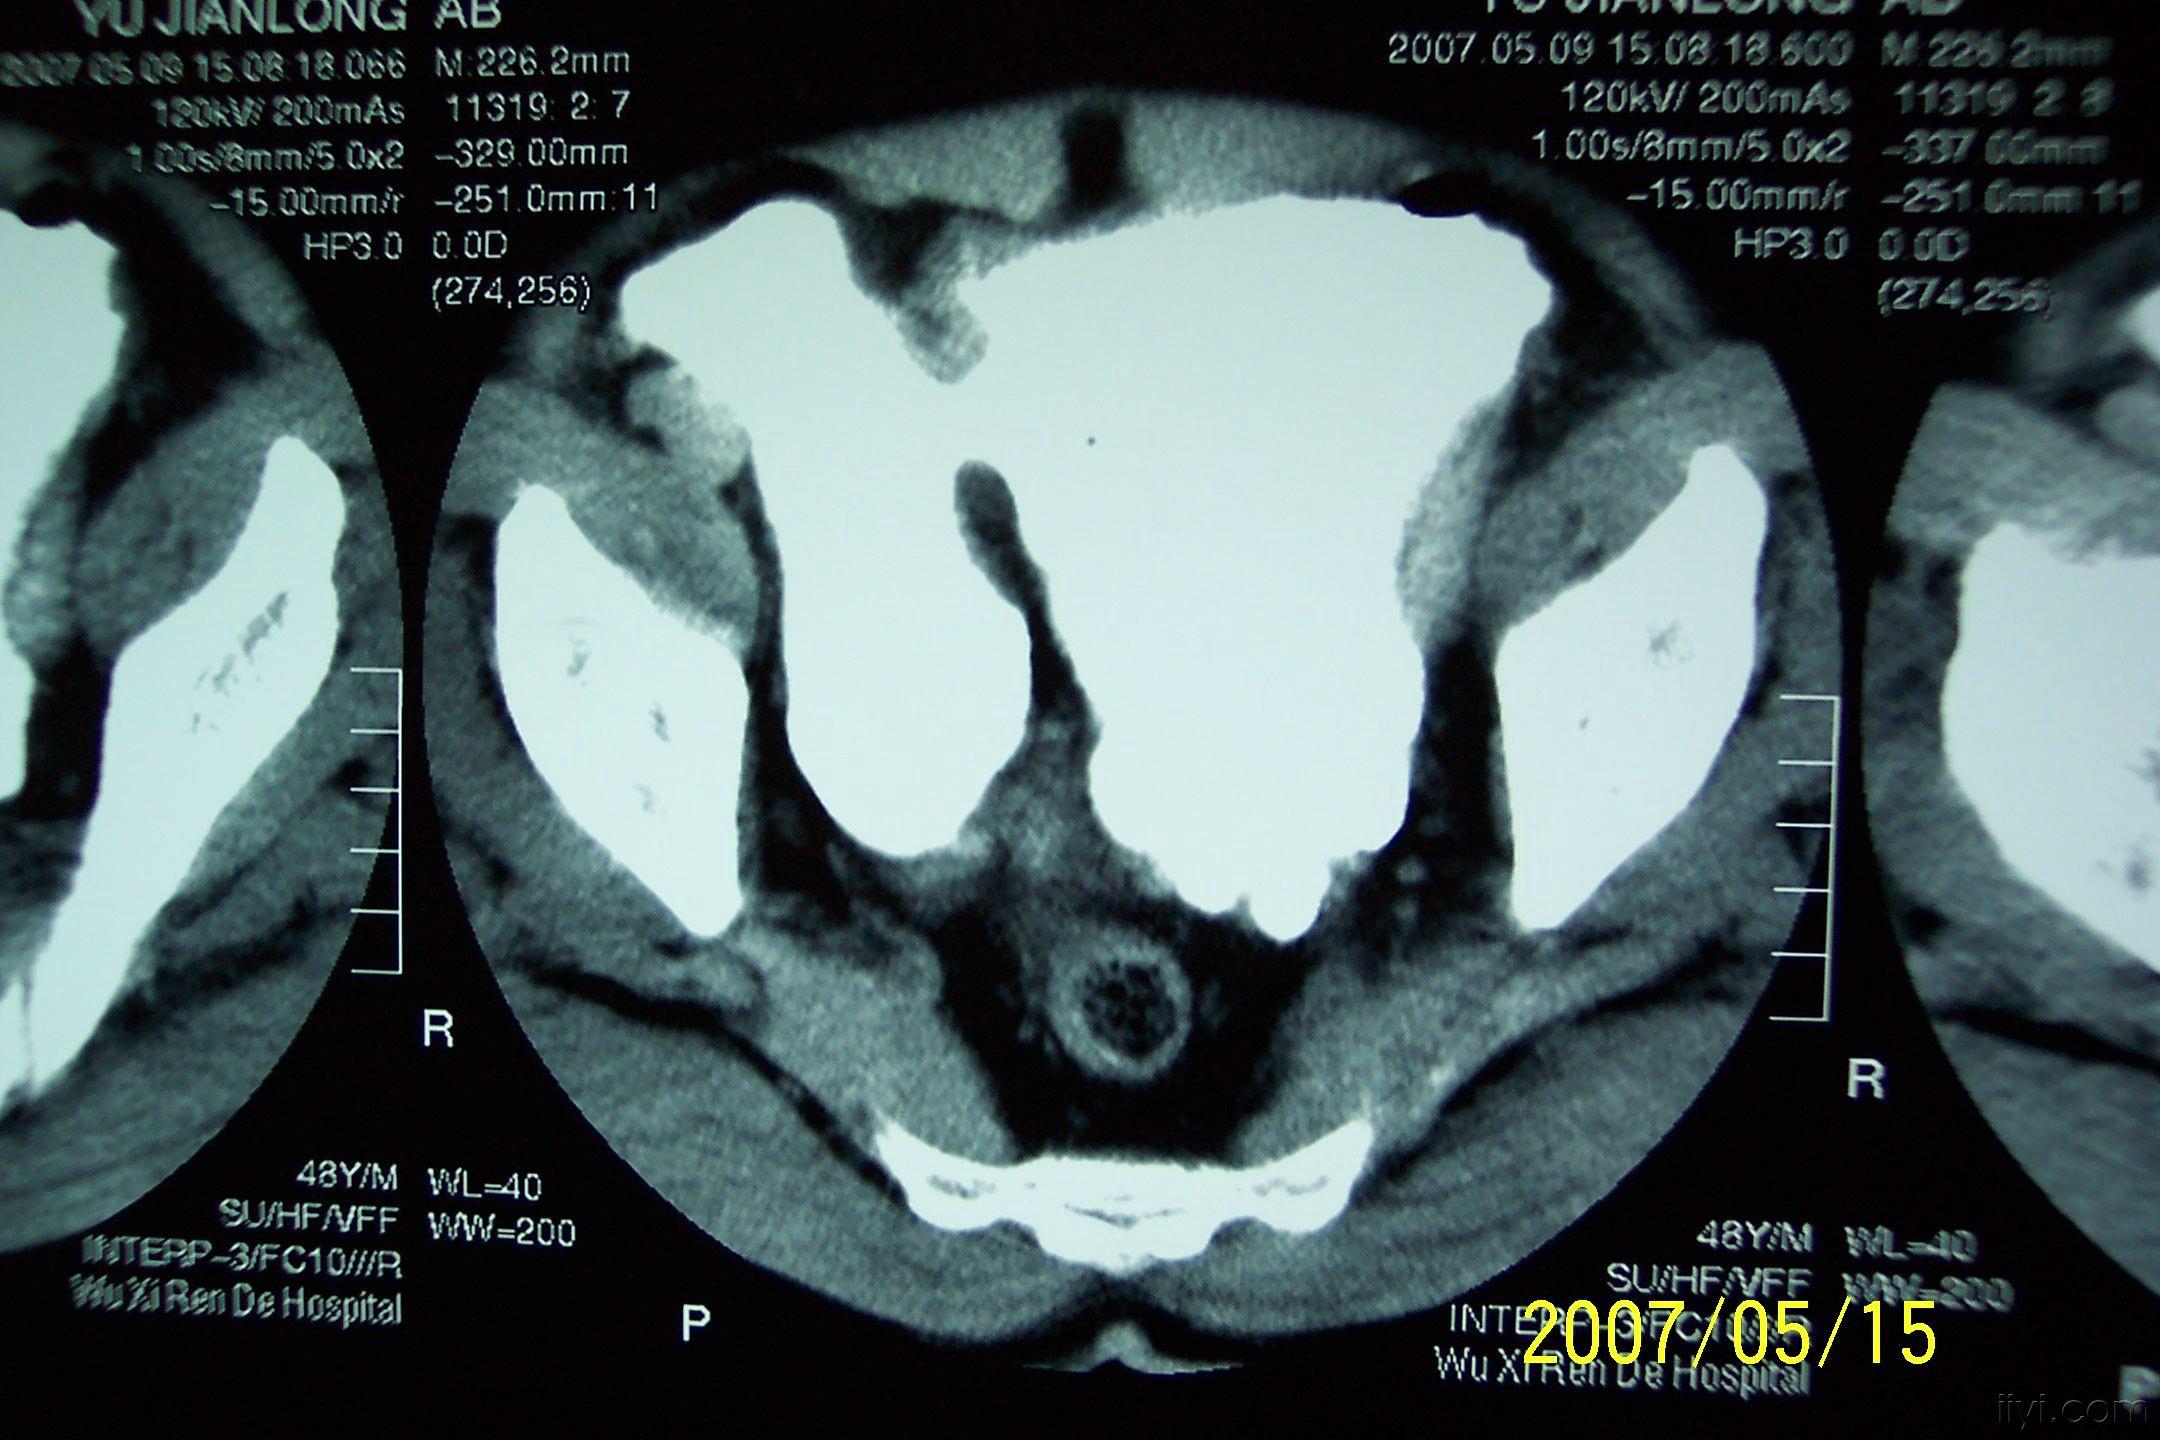

分享下一例巨大膀胱憩室的图片

分享下一例罕见病历的图片,这是我遇到的最大巨大膀胱憩室。